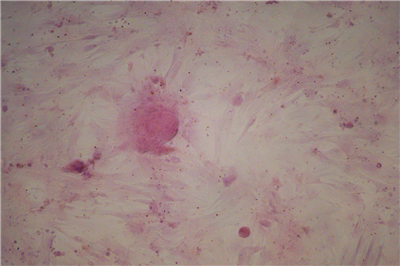

1.成骨诱导的过程是使钙离子能够以钙盐的方式沉淀下来,即“钙结节”,鉴定钙结节的染色方法常用茜素红染色法。

3.染色原理:茜素红与钙发生显色反应,产生一种深红色的带色化合物,这样成骨诱导的细胞外面沉积的钙结节也就被染成了深红色。.